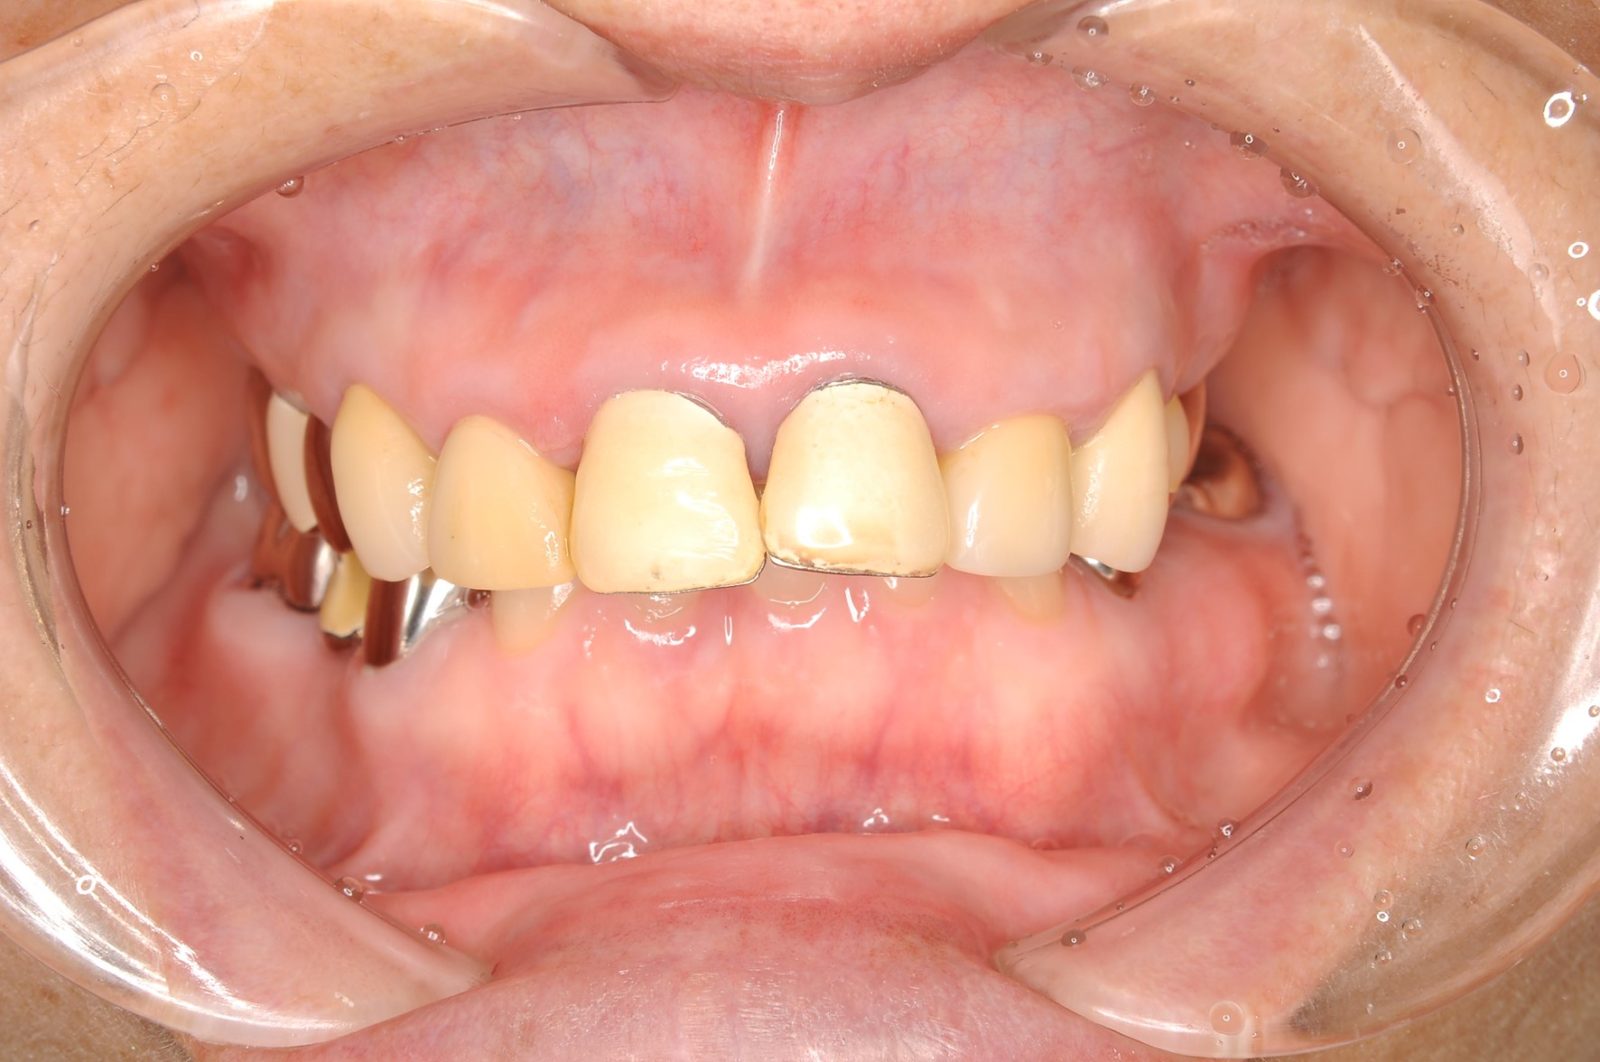

「顎のずれ」が大きい場合は、被せ物を利用し噛み合わせを再構成したり、歯列矯正により噛み合わせを整えることも行います。その方の年齢や、歯、歯肉などの状態に応じた、最適な治療方法をご提案いたします。以下の症例は、被せ物等を利用し噛み合わせを整えたケースになります。